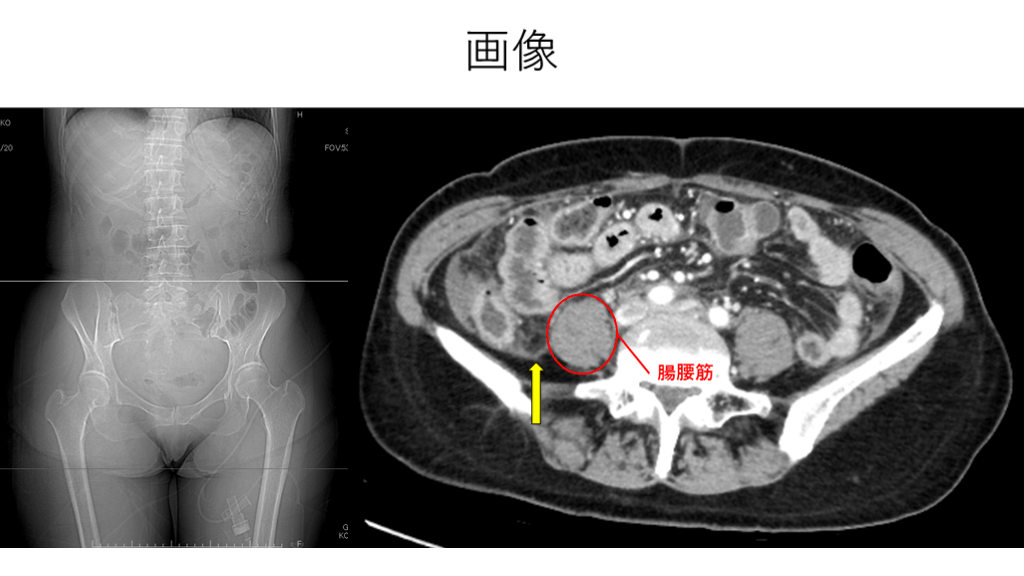

画像 腸腰筋

診断 穿孔性虫垂炎 (虫垂神経内分泌腫瘍)

Psoas line (腸腰筋陰影) 腸腰筋の外側辺縁は後腹膜の脂肪織と接している。 同部に腫瘍や炎症が生じると、腸腰筋の陰影が欠損。(陰性) シルエットサインの一種。 健常人でも20%では認められない。(特に肥満体型) 左右両側で陰性ならOKだが、片方だけ陰性なら異常を疑う。

Psoas line (腸腰筋陰影) ? 急性虫垂炎 右Psoas line 陰性 腸腰筋